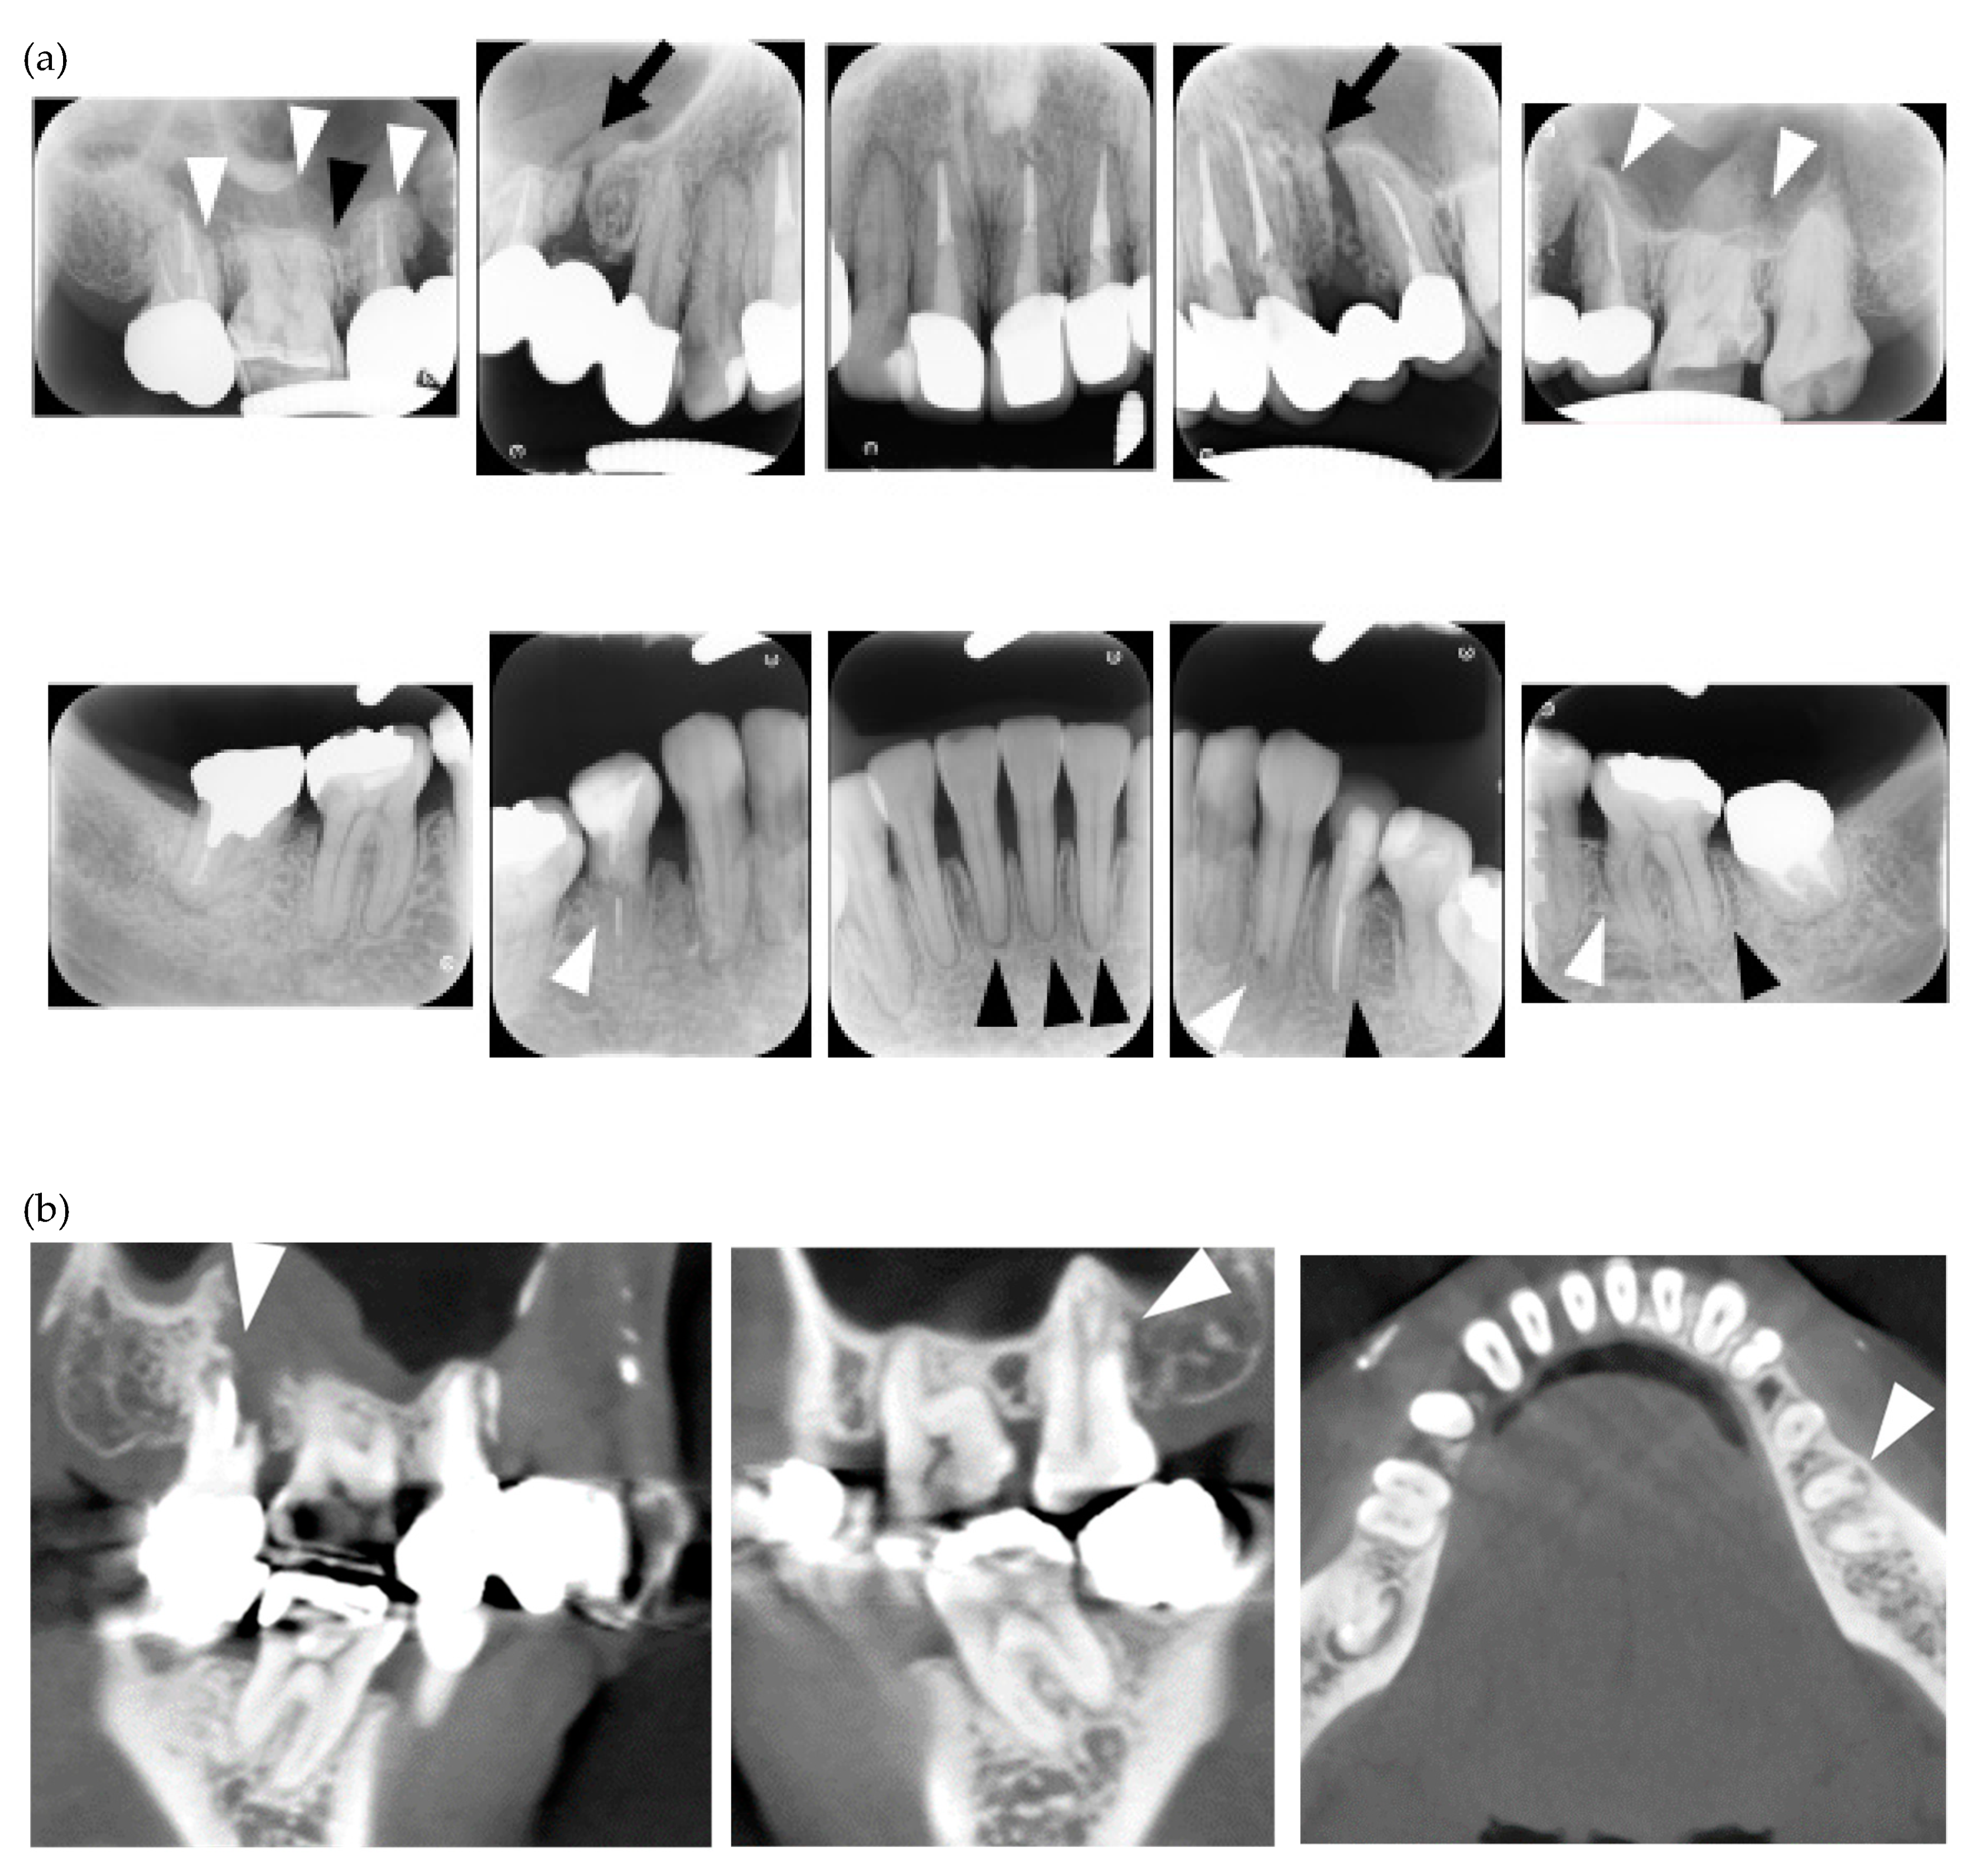

| 1 | F | 24 | lc | Y | Y | N | Y | Y | Y | Y | Y | Y | Y | / | / | / | Y | Y | N | Y | Y | Y | N | centro/RF | a case report [6]/occlusal force, 77.4N |

| 2 | F | 40 | dc | Y | Y | Y | Y | N | N | N | Y | N | Y | / | N | N | Y | Y | Y | Y | N | Y | Y | Scl-70/RF | |

| 3 | F | 23 | dc | Y | Y | Y | Y | N | Y | N | Y | Y | Y | / | / | / | Y | Y | Y | Y | Y | Y | Y | ANA/Scl-70/SS-A | Orthodontic treatment |

| 4 | F | 11 | dc | Y | Y | Y | Y | Y | N | N | N | N | Y | / | / | / | Y | Y | Y | N | N | Y | Y | ANA/Scl-70 | calcification in PDL space/Orthodontic treatment |